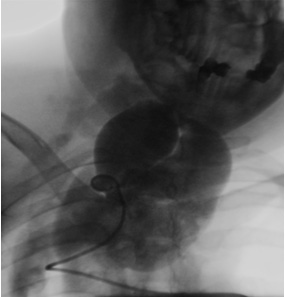

Ангиография брахиоцефальных артерий: восходящая аорта, дуга, нисходящая аорта без патологических изменений. Проксимальный сегмент правой позвоночной артерии извит, расширен. Визуализируется гигантское мешковидное образование размером 85×130 мм от уровня С5, занимающее всю область шеи, подчелюстную область и спускающееся в грудную полость по ходу верхней полой вены (рис.5). Отмечается сужение правой подключичной артерии до 80% при выходе из реберно-ключичного пространства. Правая общая сонная артерия — девиация в среднем отделе. Выполнена ангиография брахиоцефальных сосудов и селективная ангиография полости аневризмы. Верхняя граница аневризмы визуализируется до интракраниального отдела правой позвоночной артерии. При ангиографии левой позвоночной артерии выявлен переток в систему правой позвоночной артерии с контрастированием аневризмы (рис.6). Левые позвоночная, общая сонная артерия — без особенностей. Клинический диагноз: Гигантская аневризма правой позвоночной артерии. Миелопатия от длительного сдавления в шейном отделе позвоночника смешанного генеза (компрессионная, ишемическая). Дисциркуляторная энцефалопатия в вертебро-базилярном бассейне. Нейрофиброматоз I типа (синдром Реклингаузена). Медикаментозное лечение: детралекс, дексазон, эуфиллин, карнитин, мексидол. Учитывая, что полость аневризмы заполнялась как антеградно, так и ретроградно (через базилярную артерию), было решено первым этапом локализовать аневризматический мешок в дистальном отделе эмболизацией позвоночной артерии спиралями GIANTURCO (COOK) доступом через контрлатеральную позвоночную артерию. Однако, в связи с техническими трудностями прохождения проводника и катетера через базилярную артерию, решено воздержаться от выполнения данной процедуры и попытаться закрыть аневризму из антеградного доступа имплантацией устройства «Amplatzer» для закрытия открытого артериального протока в проксимальный отдел правой позвоночной артерии.

26.12.2003г. проведена эндоваскулярная операция — закрытие аневризмы с помощью устройства «Amplatzer duct occluder» (рис.7 ).

Рис.5 Ангиография аневризмы правой позвоночной артерии.

Рис.6 Ангиография левой позвоночной артерии. Антеградное заполнение полости аневризмы.